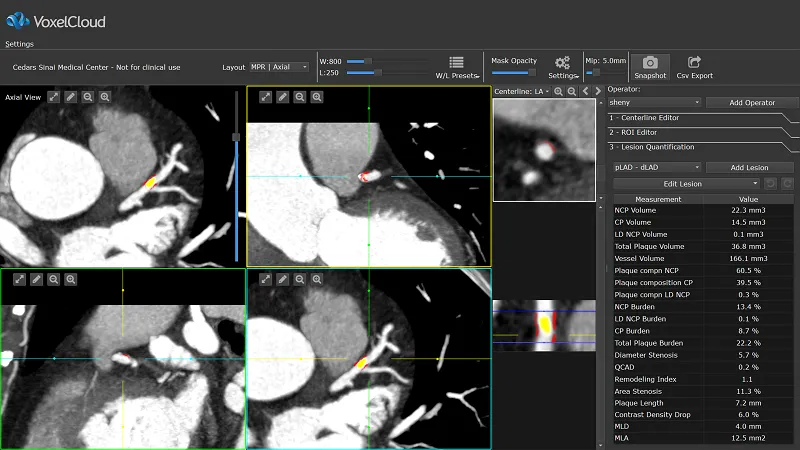

眼下,基于大量的深度访谈和统计数据,体素科技为医院和体检中心提供针对影像类型的智能阅片解决方案,自动诊断和撰写影像视野可见范围内的所有异常,譬如胸部CT、心脏冠脉造影CT等。

不过,他也提到,像一些对临床工作流程改变较大,甚至使用了全新生物标志物的产品,就需要一定的临床证据收集后对市场教育才可以推开。

冠脉CT产品